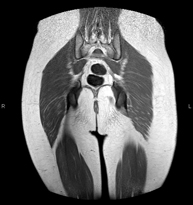

- RM Glúteos

Exploración para el estudio de la musculatura y de los tendones que se originan a este nivel, como los tendones isquiotibiales, frecuentemente lesionados en deportistas. Tiene una duración aproximada de 16 minutos. No emplea radiación ionizante.